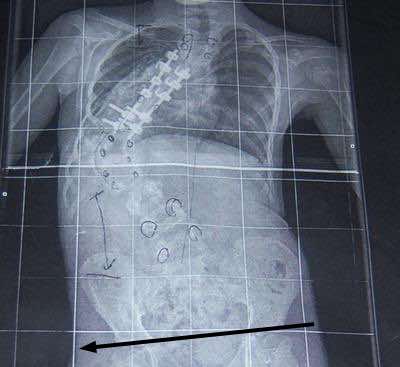

I don't think it takes much imagination to see that a short leg was in part the cause of the scoliosis above.